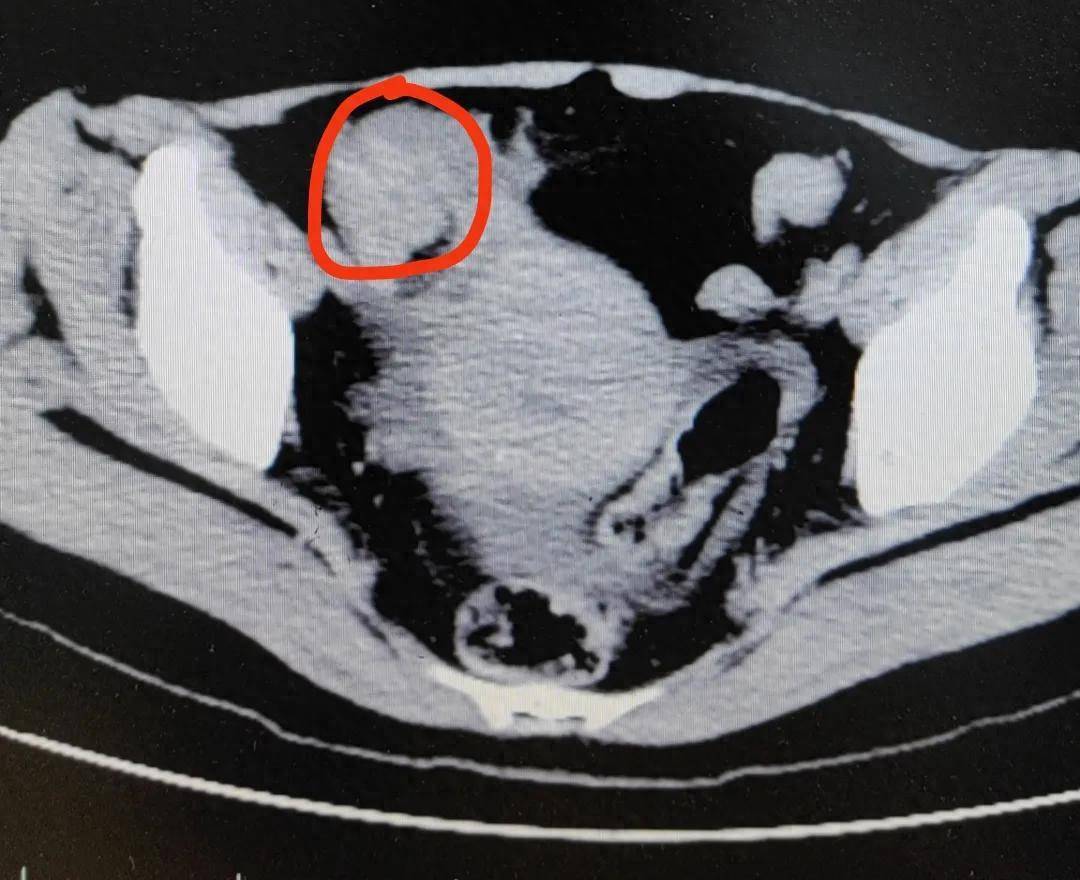

据杭州市一病院音问,患者冯女士(化姓)在家不息连吃3个柿子,晚餐又吃了2只大闸蟹。效用今日晚上,冯女士瞬息运行肚子痛,痛得全身冒盗汗,还遏抑吐逆。忍了两天后,冯女士终于到病院就诊。

经查验,医师怀疑冯女士发生了绞窄性肠淆乱,手术从肠子里切出一堆“石头”,也即是俗称的“柿石症”,最大的直径有4厘米!